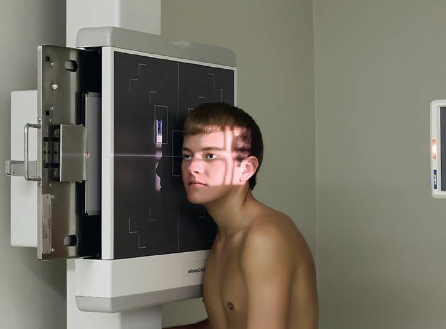

Axiolateral (modified Schuller) TMJs

patient position:

right or left lateral, both sides done for comparison

semiprone or upright

part position:

center ½ inch anterior to the EAM to the IR

head in true lateral

MSP parallel with IR

IPL perpendicular

one exposure with the mouth closed, and a second with the mouth open (if not contraindicated

respiration suspended

CR:

25-30 caudad

enters ½ inch anterior and 2 inches superior to upside EAM

collimation:

1 inch betond the anterior skin line, posteior and inferior to the TMJs